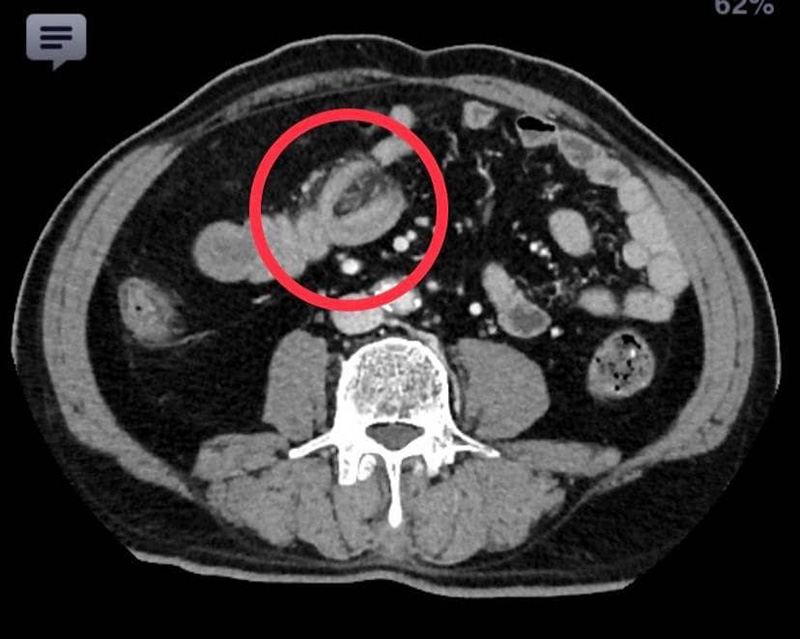

แพทย์ห้องฉุกเฉิน เห็นว่าผู้ป่วยเป็นผู้สูงอายุและเป็นมานาน ควรจะได้รับการตรวจวินิจฉัยโดยละเอียด จึงปรึกษาอายุรแพทย์ ศัลยแพทย์ และรังสีแพทย์ ไปพร้อม ๆ กัน จนได้ภาพรังสีจากเอกซเรย์คอมพิวเตอร์ออกมา พบว่ามีส่วนของลำไส้เล็กส่วนปลายกลืนกัน จึงวางแผนรักษาโดยการผ่าตัดทันที